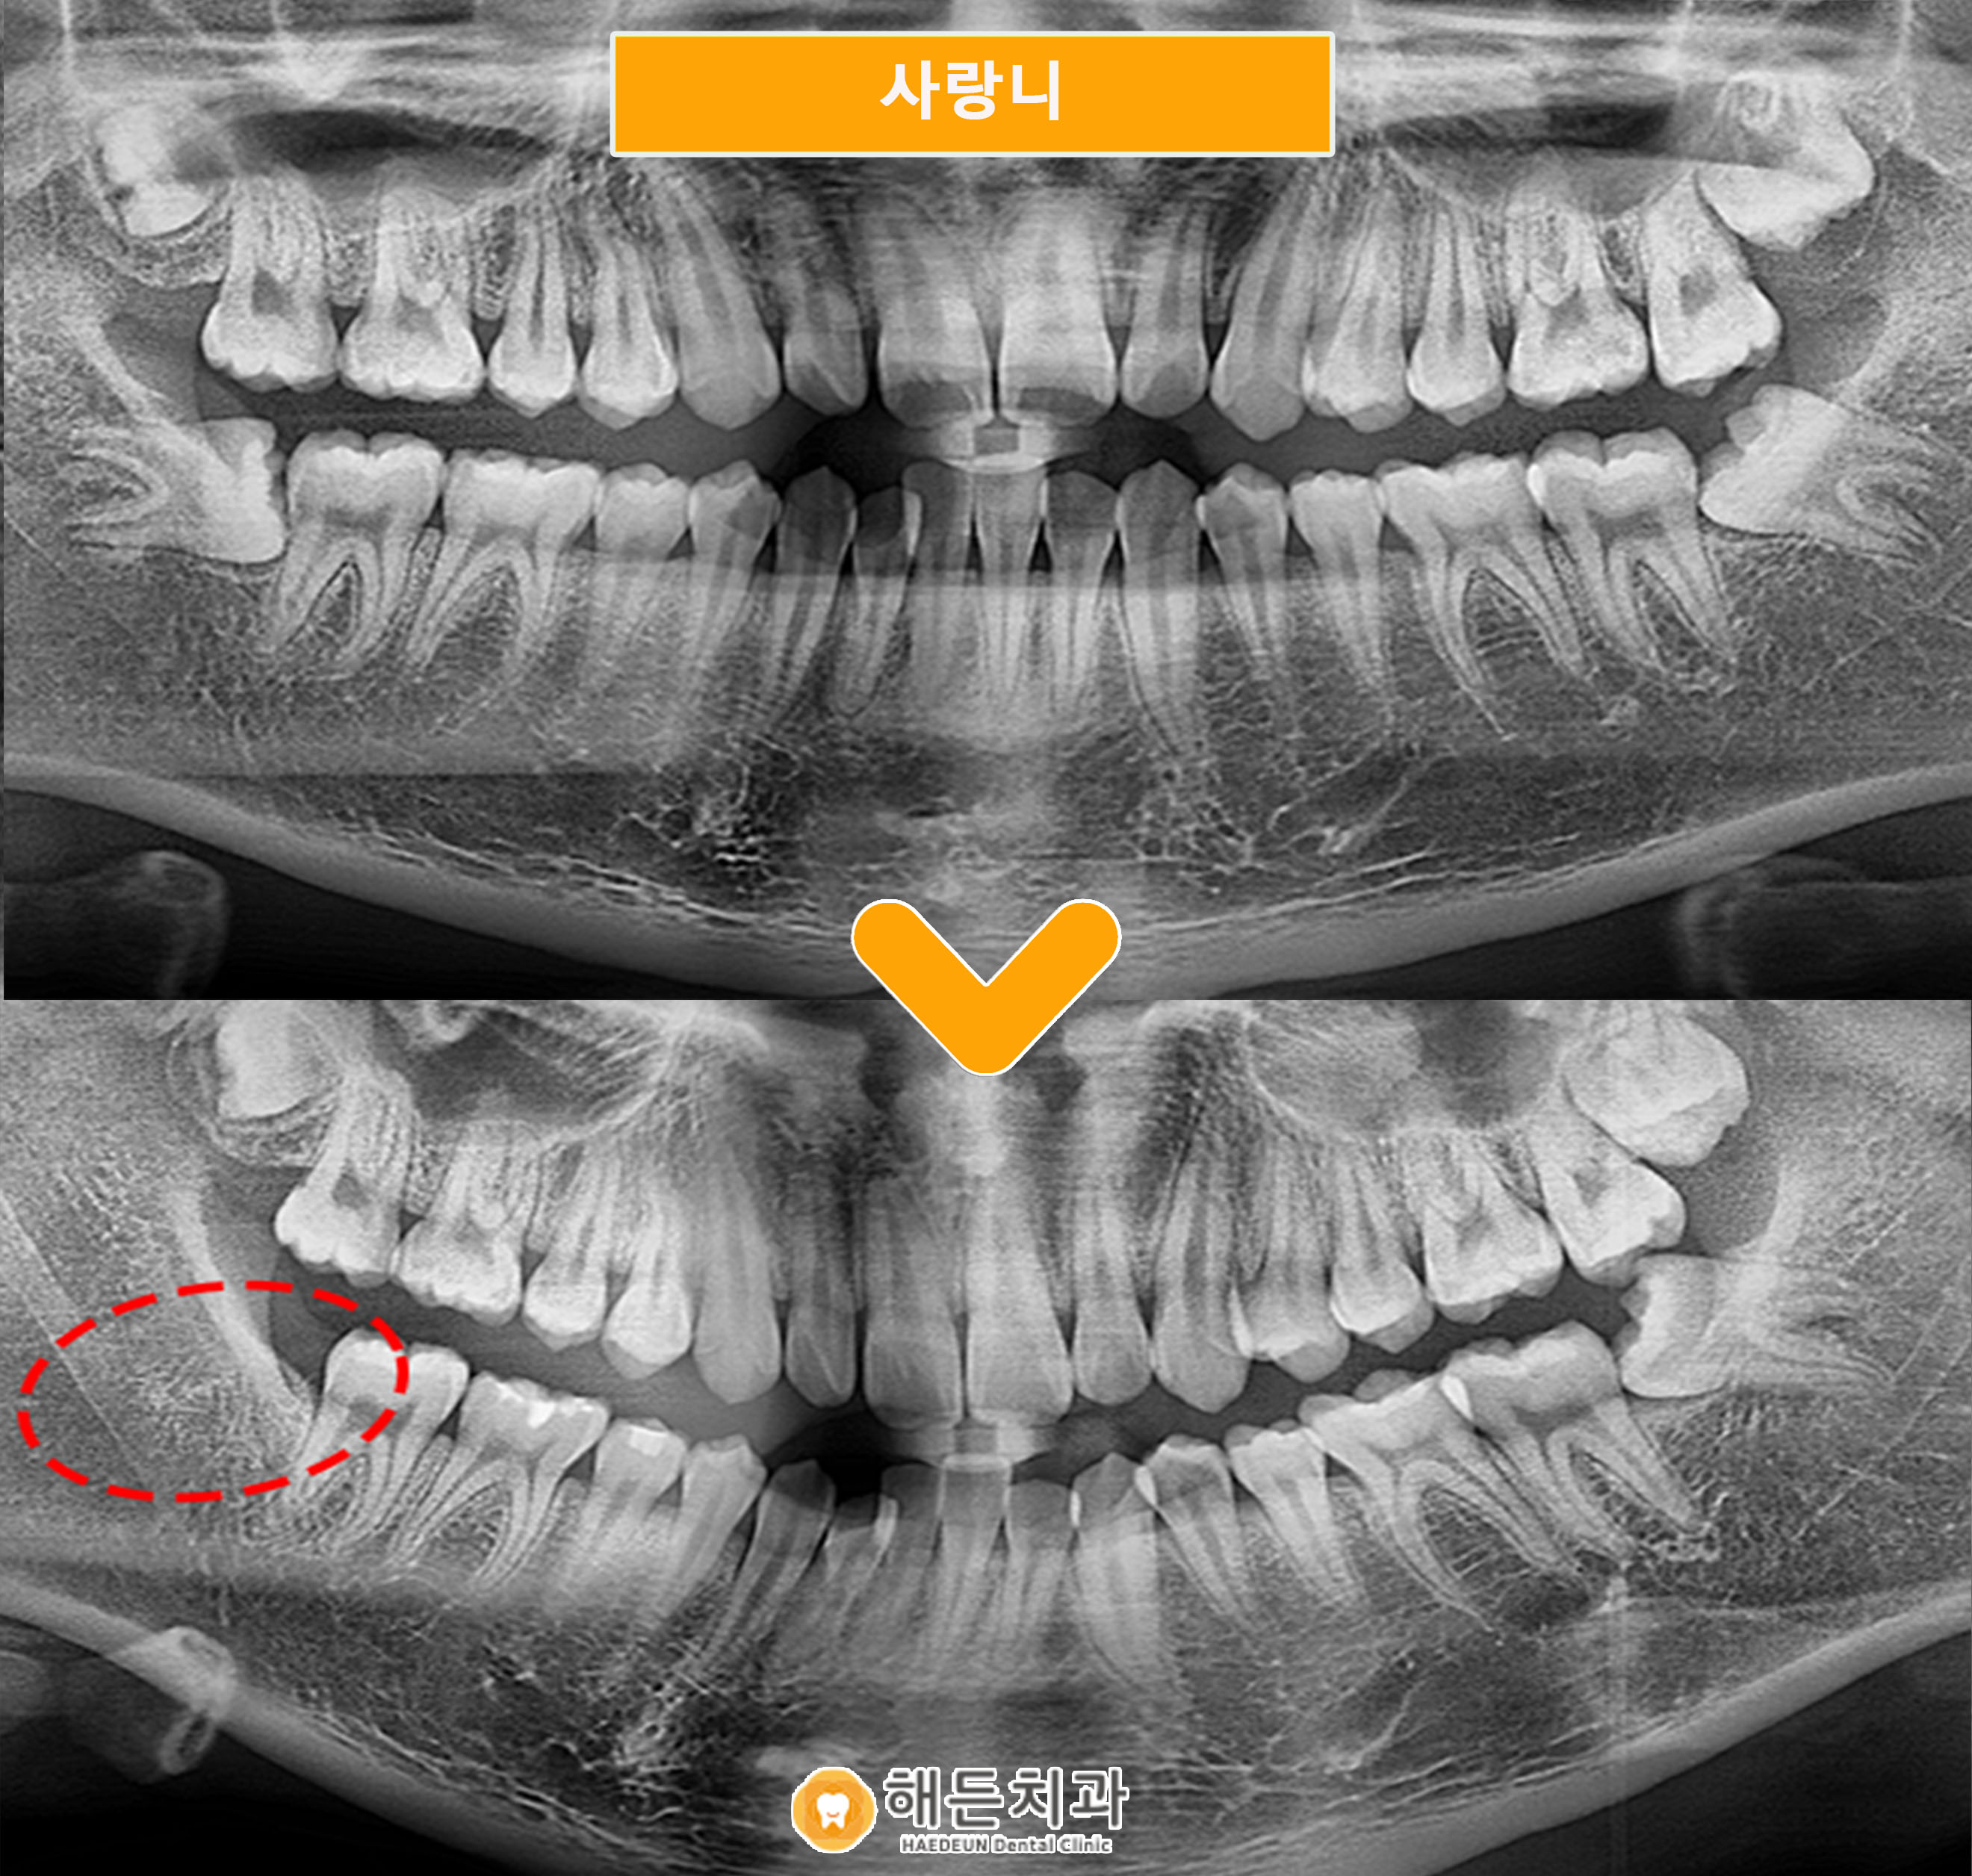

치아 통증으로 해든치과에 내원하신 환자분의 사례로,

파노라마 및 구강 사진을 통해 해당 치아가

정상적인 방향이 아닌 옆으로 기울어진 상태에서

일부만 맹출한 양상을 확인할 수 있었습니다.

.

이처럼 치아가 절반 정도만 올라온 경우에는

앞쪽 어금니와의 사이에 음식물이나 이물질이

쉽게 끼는 환경이 형성되며,

관리가 어려워지는 경향이 나타납니다.

실제로 아산배방치과의 구강 사진에서도

인접 치아와 맞닿는 부위에 변화가

의심되는 부분이 관찰되었습니다.